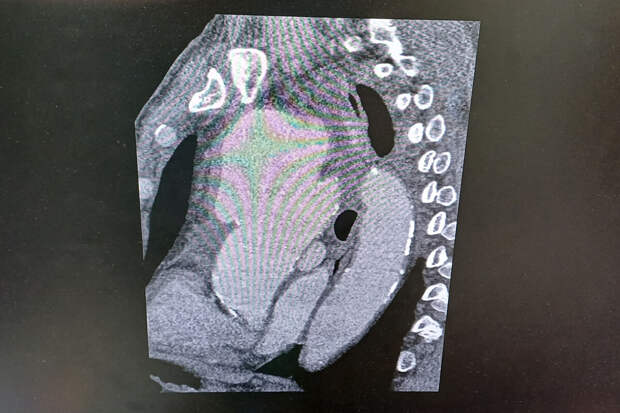

На скорой пациента доставили в кардиоцентр. Медики отметили, что "в организме мужчины, фактически, находилась мина замедленного действия, которая в любой момент могла разорваться"."Компьютерная томограмма подтвердила выпячивание аорты размером 9 на 9 сантиметров. Гигантская мешотчатая аневризма, больше, чем гусиное яйцо", - рассказал заведующий отделением №5 Рязанского кардиодиспансера Сергей Загородний.

По словам специалиста, аневризма сдавливала все близлежащие органы и ткани: трахеи, бронхи, верхнюю полую вену.